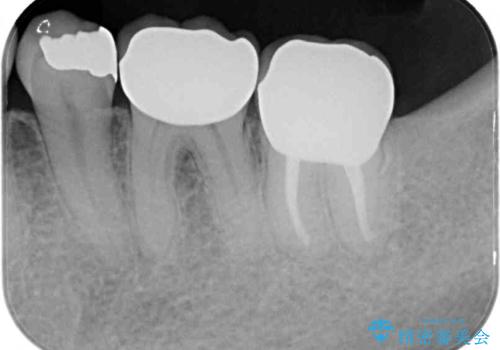

- 奥歯を他院で抜歯した後、インプラント治療を希望とのことで来院された患者様です。

ブリッジの支台を抜歯したことで2本のインプラントが必要であり、その後方はインプラント埋入に必要な骨量が不足していたため、上顎洞粘膜の挙上を行うこととしました。

また、残っている最後方歯は手前に倒れてきていたため、部分矯正により奥に移動させてから、インプラント埋入を行うこととしました。